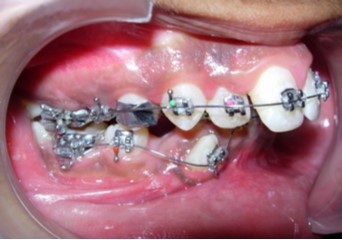

Initial alignment was done with upper and lower 0.014-inch nickel titanium archwires (Figure 6a,Figure 6b,Figure 6c). This was followed with 0.016-inch nickel titanium archwires. Space for blocked out 42 was created by an open coil spring on a 0.018-inch stainless steel archwire. Deep bite was corrected with a lower 0.016-inch reverse curve nickel titanium wire. Extraction spaces in the maxillary and mandibular dental arches were closed with 9mm nickel titanium retraction coil springs attached to crimpable hooks on 0.017 x 0.025-inch stainless steel archwires and finishing and detailing was completed with 0.019 x 0.025-inch stainless steel archwires.

Figure 6a.Initial levelling and alignment – Upper / Lower 0.014-inch nickel titanium wires – Frontal

Figure 6b.Initial levelling and alignment – Upper / Lower 0.014-inch nickel titanium wires – Right

Figure 6c.Initial levelling and alignment – Upper / Lower 0.014-inch nickel titanium wires – Left